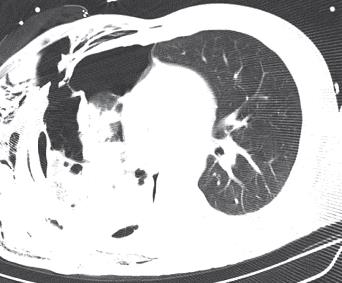

- 15.4. Mellkasi sérülések ellátása rendkívüli körülmények között